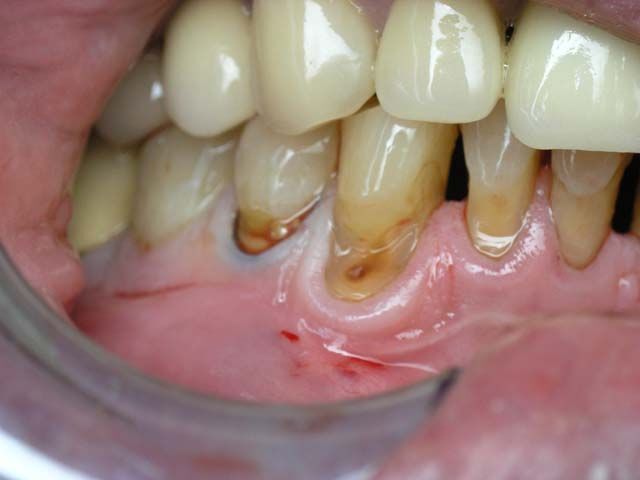

Одной из самых распространенных стоматологических болезней является прикорневой кариес, который поражает зубные ткани у корня, на границе зуба с десной, и даже может выходить за пределы коронковой части. Разрушительный процесс в этой зоне обычно развивается весьма стремительно, поскольку эмаль здесь имеет минимальную толщину: воспаление быстро проникает в глубинные слои зуба, затрагивая корневые каналы.

• образование полости на границе с десной.

Лечение прикорневого кариеса требует от стоматолога большого профессионализма, поскольку проблемная зона обладает повышенной чувствительностью и располагается в непосредственной близости с десной. Другая сложность заключается в том, что в прикорневой области пломбы плохо держатся, поэтому необходимо подобрать материал, отличающийся высокой адгезией.